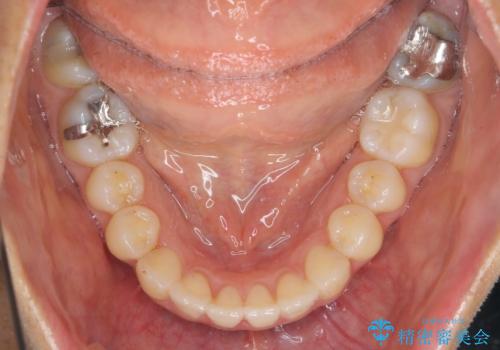

- 気になる前歯のガタつきをマウスピースで治療したいと希望され来院されました。

当日に矯正検査を行い、骨格・歯に問題がないことを確認しマウスピースによる矯正治療を進めます。

IPRを前歯部に少量行うことで、非抜歯でも前歯が外に飛び出さない仕上がりを達成できました。